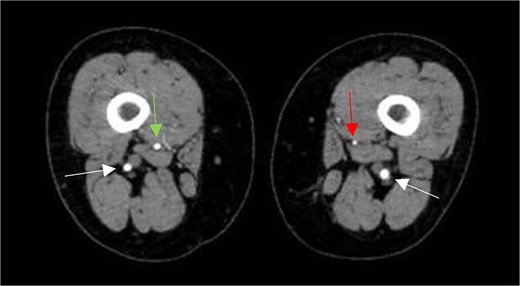

Subsequently, the patient underwent computed tomography angiography (CTA) of the lower extremities which revealed bilateral PSA (Fig. 1). The common femoral arteries trifurcated normally (Fig. 2), but the left superficial femoral artery (SFA) was significantly narrowed (Fig. 3). At the level of the knee, the right SFA joined the PSA to form the popliteal artery (Fig. 4). On the left side, the hypoplastic SFA converged with the PSA more proximally (Fig. 4); however, the artery was occluded, with no clear continuation into the popliteal artery (Fig. 4). Nevertheless, a markedly sub-occluded left popliteal artery was noted at the level of the fibular head, giving rise to a hypoplastic anterior tibial artery and tibio-peroneal trunk (Fig. 4). These findings align with Ahn-Min’s type I bilateral PSA (Fig. 5).

Axial CTA image shows hypoplastic left SFA along its course in the adductor canal (vertical arrow on left leg), but normal-sized right SFA (vertical arrow on right leg), and bilateral prominent PSAs (horizontal arrows).